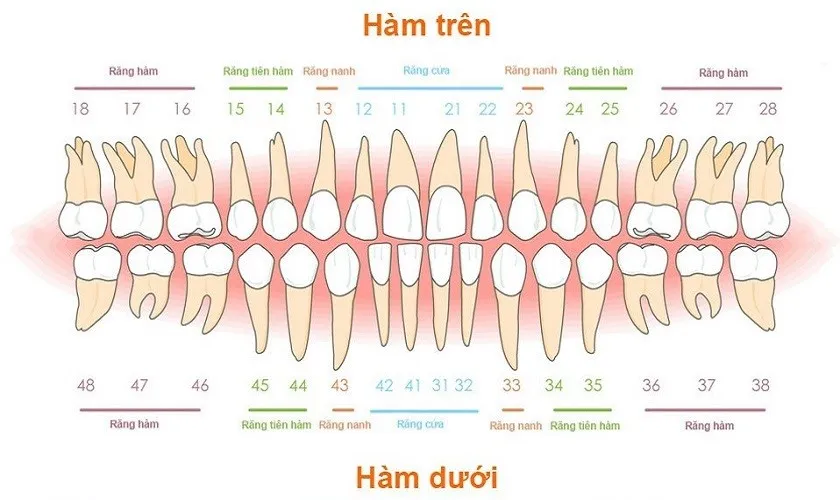

Các loại hàm răng là kiến thức cơ bản nhưng vô cùng quan trọng trong việc hiểu và chăm sóc sức khỏe răng miệng. Dù bạn đang